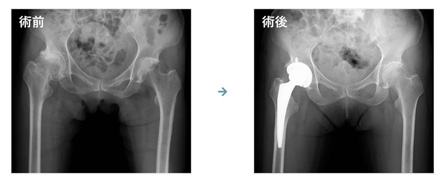

人工股関節置換術(Total Hip Arthroplasty:THA)とは、傷んで変形した関節を人工物で作られた関節に置き換える手術です。

人工股関節置換術(THA)には様々な方法があります。

変形の程度や患者さまの特性にあわせて、最適と考えられる方法を提供します。

• 画像:人工股関節置換術

• 画像:大腿骨壊死症

画像:日本整形外科学会